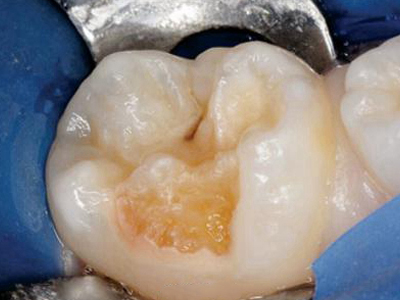

牙齿

大坑

牙釉质发育不全牙齿棕色凹坑图

牙釉质发育不全患者的磨牙表面少了一块,出现凹陷性的大坑,坑内微微泛黄呈棕色,凹凸不平,患者自觉无明显不适症状,建议进行牙齿修复治疗。